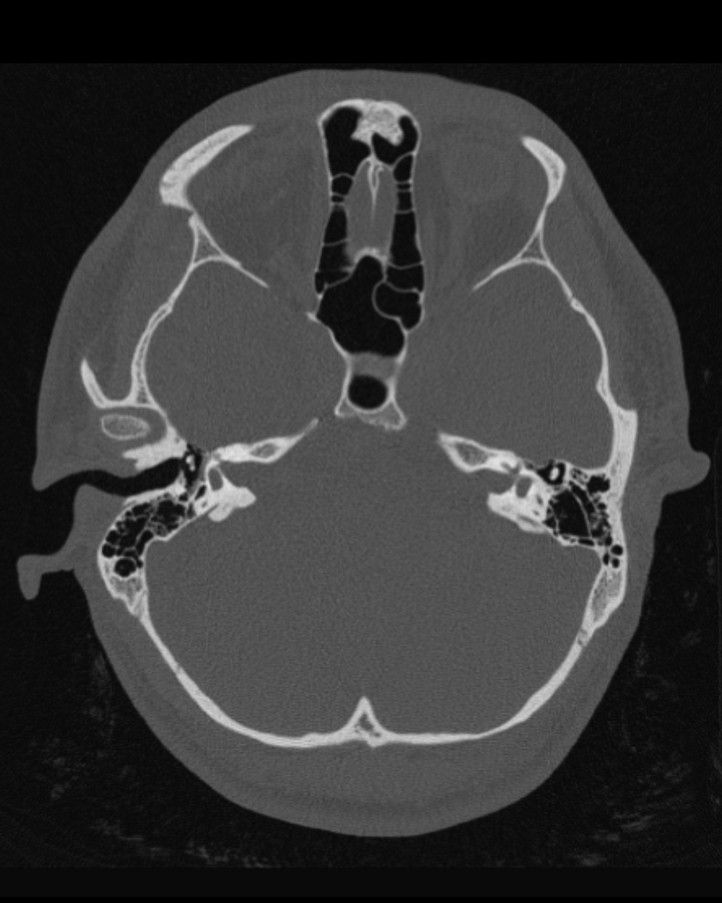

Radiology

- CT: shows temporal bone & middle ear, ossicles, cholesteatoma (squamous epithelium trapped in the middle ear)

- MRI: shows facial nerve (often displaced in middle ear malformations) (Calzolari, 1999 & Carvalho, 1999).

This can be seen in the images below.

Grade III Microtia on the Left - Case courtesy of Assoc Prof Frank Gillard